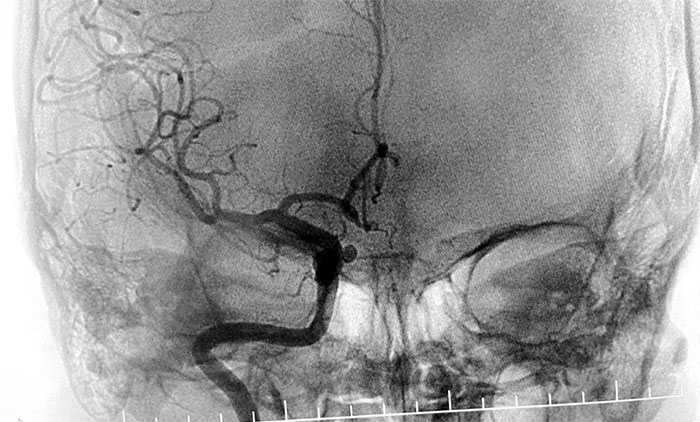

患者入院後,餘志良主任為患者完善查體,根據病情特點,着重排查腦血管疾病可能。通過CTA檢查,發現右側頸內動脈C6段動脈瘤。醫院學術副院長、神經內科4A病區主任席剛明教授團隊進一步行DSA腦血管造影檢查,提示右頸內動脈眼動脈段動脈瘤。

▲ DSA檢查提示,右頸內動脈眼動脈段動脈瘤

通過審慎討論評估,餘志良主任和席剛明教授一致認為,該部位動脈瘤可因壓迫重要血管神經,引起頭痛頭暈、視覺障礙等相關症狀。一旦發生破裂出血,可導致患者出現一系列嚴重的神經功能損害,甚至危及生命。